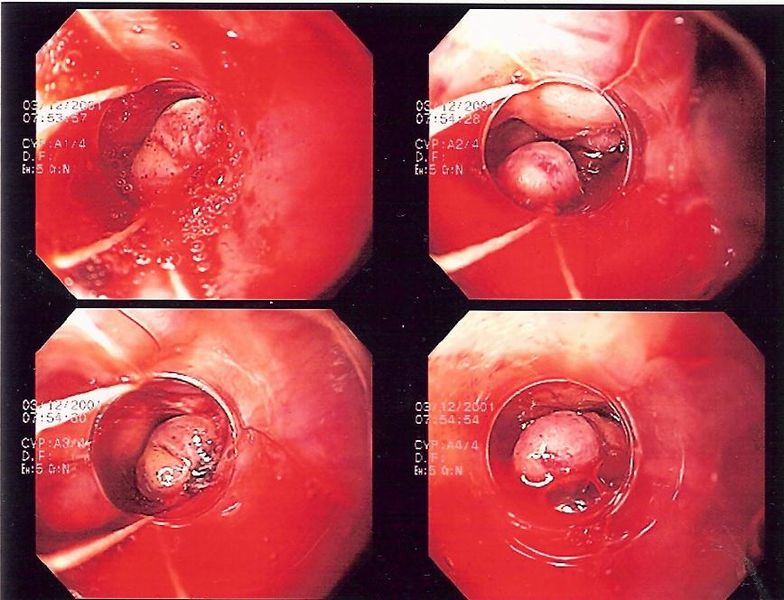

- Oesophageal varices – needs urgent endoscopy and concurrent resuscitation with blood products, alongside prophylactic antibiotics and somatostatin analogues (e.g. terlipressin or octreotide, to reduce splanchnic blood flow) to be given

- Endoscopic banding is the most definitive method of management but can be technically difficult (Fig. 4); a Sengstaken-Blakemore tube can be used in severe or uncontrollable cases as a temporary control to compress the bleeding

Figure 4 – Endoscopic banding of bleeding oesophageal varices